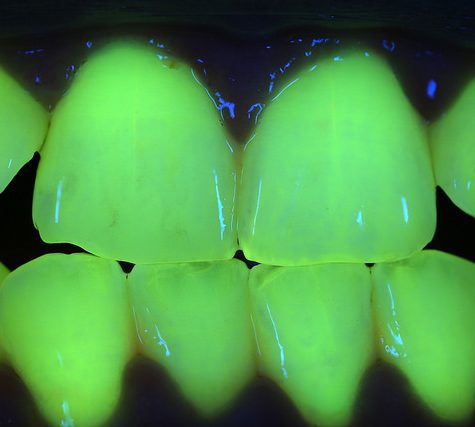

A tooth (plural teeth) is a hard, calcified structure found in the jaws (or mouths) of many vertebrates and used to break down food. Some animals, particularly carnivores, also use teeth for hunting or for defensive purposes. The roots of teeth are covered by gums. Teeth are not made of bone, but rather of multiple tissues of varying density and hardness. The cellular tissues that ultimately become teeth originate from the embryonic germ layer, the ectoderm.

A tooth (plural teeth) is a hard, calcified structure found in the jaws (or mouths) of many vertebrates and used to break down food. Some animals, particularly carnivores, also use teeth for hunting or for defensive purposes. The roots of teeth are covered by gums. Teeth are not made of bone, but rather of multiple tissues of varying density and hardness. The cellular tissues that ultimately become teeth originate from the embryonic germ layer, the ectoderm.

A tooth (plural teeth) is a hard, calcified structure found in the jaws (or mouths) of many vertebrates and used to break down food. Some animals, particularly carnivores, also use teeth for hunting or for defensive purposes. The roots of teeth are covered by gums. Teeth are not made of bone, but rather of multiple tissues of varying density and hardness. The cellular tissues that ultimately become teeth originate from the embryonic germ layer, the ectoderm.

A tooth (plural teeth) is a hard, calcified structure found in the jaws (or mouths) of many vertebrates and used to break down food. Some animals, particularly carnivores, also use teeth for hunting or for defensive purposes. The roots of teeth are covered by gums. Teeth are not made of bone, but rather of multiple tissues of varying density and hardness. The cellular tissues that ultimately become teeth originate from the embryonic germ layer, the ectoderm.

A tooth (plural teeth) is a hard, calcified structure found in the jaws (or mouths) of many vertebrates and used to break down food. Some animals, particularly carnivores, also use teeth for hunting or for defensive purposes. The roots of teeth are covered by gums. Teeth are not made of bone, but rather of multiple tissues of varying density and hardness. The cellular tissues that ultimately become teeth originate from the embryonic germ layer, the ectoderm.

A tooth (plural teeth) is a hard, calcified structure found in the jaws (or mouths) of many vertebrates and used to break down food. Some animals, particularly carnivores, also use teeth for hunting or for defensive purposes. The roots of teeth are covered by gums. Teeth are not made of bone, but rather of multiple tissues of varying density and hardness. The cellular tissues that ultimately become teeth originate from the embryonic germ layer, the ectoderm.